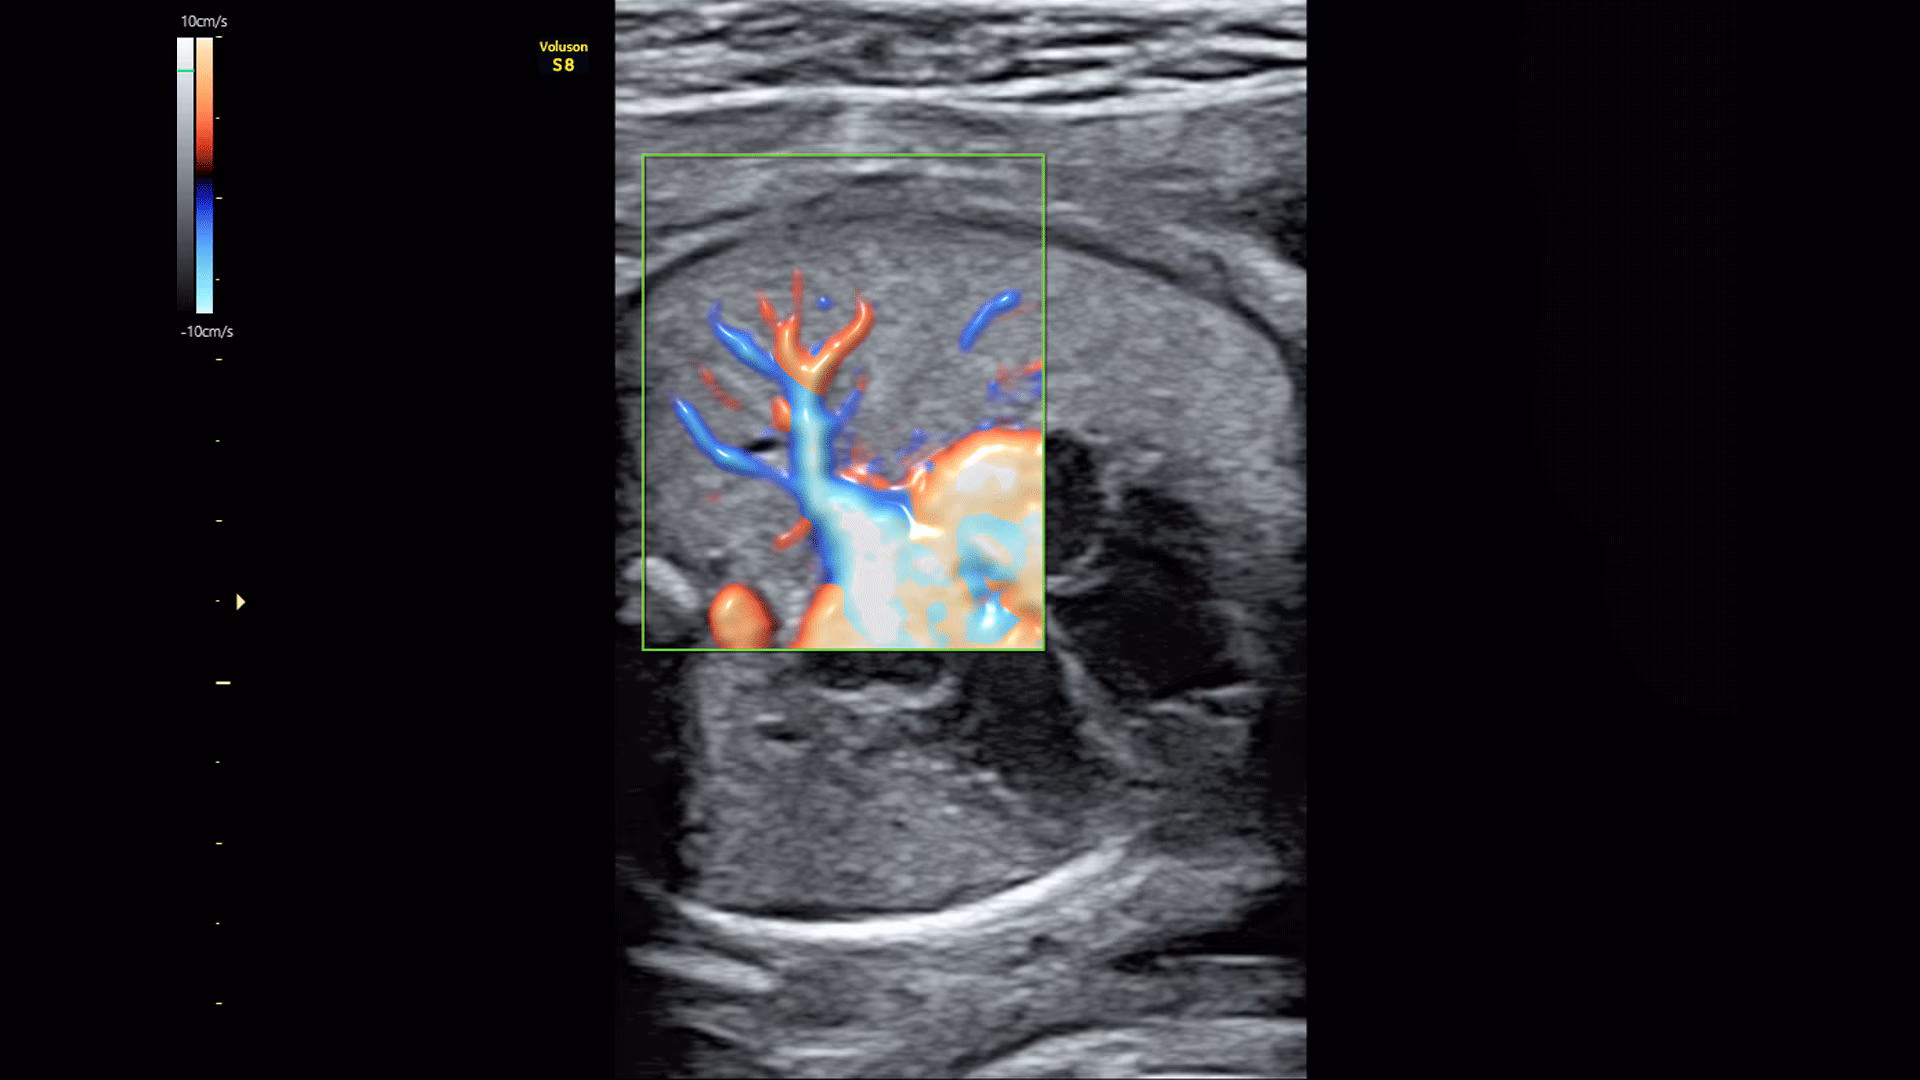

Sistema ecografico per ostetricia, ginecologia e fertilità

VOLUSON S8 con Touch panel

- Visualizzazione dei piccoli vasi e dei bordi nel cuore fetale con RadiantFlowTM